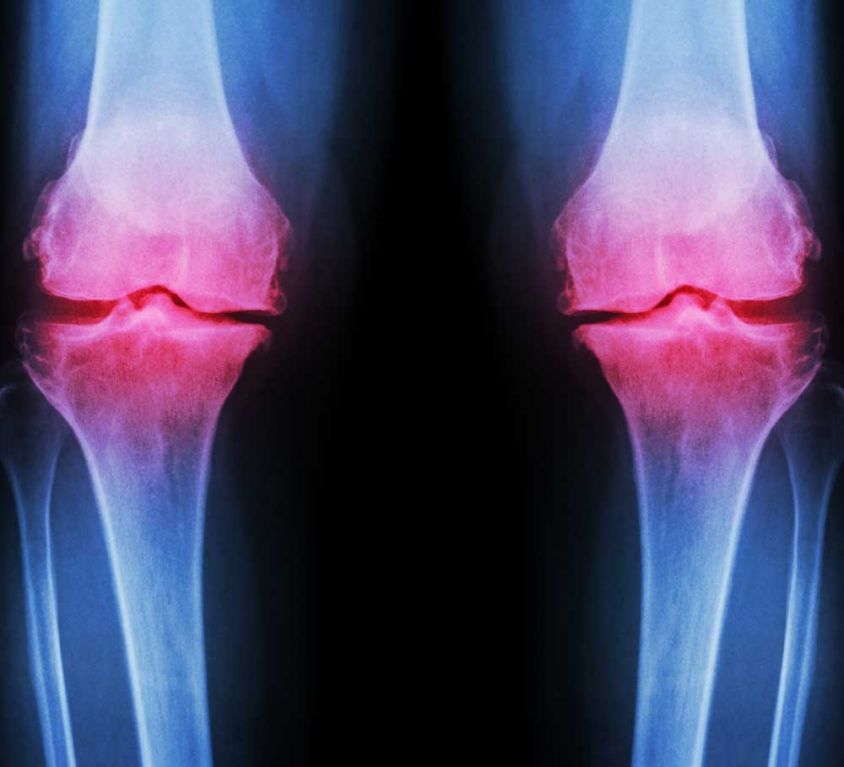

Knee surgery is often used for the treatment of different conditions that can cause knee pain. While non-surgical treatments are often attempted for initial treatment, there are situations where knee surgery becomes the recommended or necessary treatment.